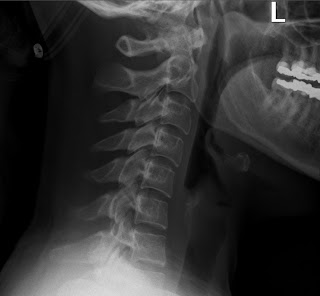

Recently I have seen a lot of patients that are suffering because of what is called anterior head carriage. Anterior head carriage is when the weight of the head (8-9lbs) is brought forward. This exerts extreme amount of pressure on the spine. The head is then left in this position for an extended period of time, resulting in muscle inflammation and trigger points. Here is a normal side view x-ray (mine).

notice the smooth upward curve.